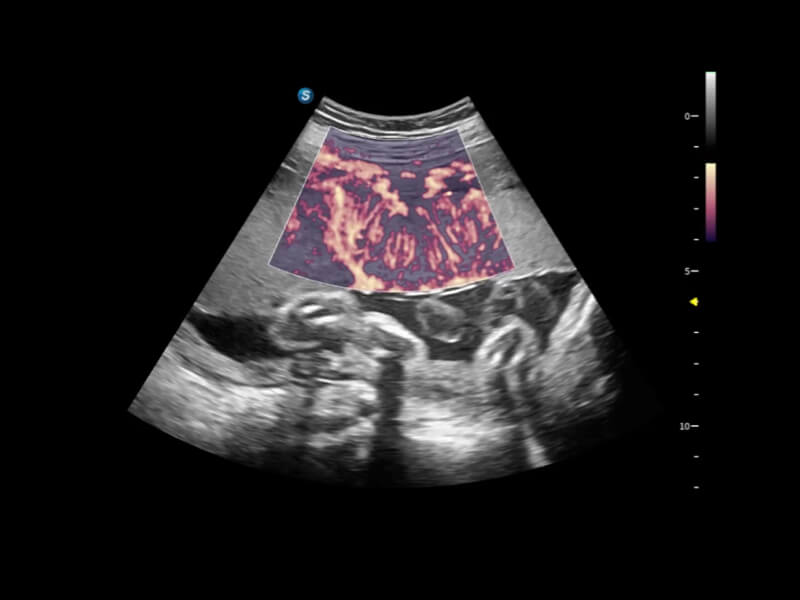

通过创新的Matrix E自适应滤波算法,能有效滤除软组织和噪声信号,最大限度保留超低速微细血流的信号;结合超长时间域算法,极大提升细微血流的敏感性和空间分辨率,更真实的反应组织、包块的血流灌注情况。